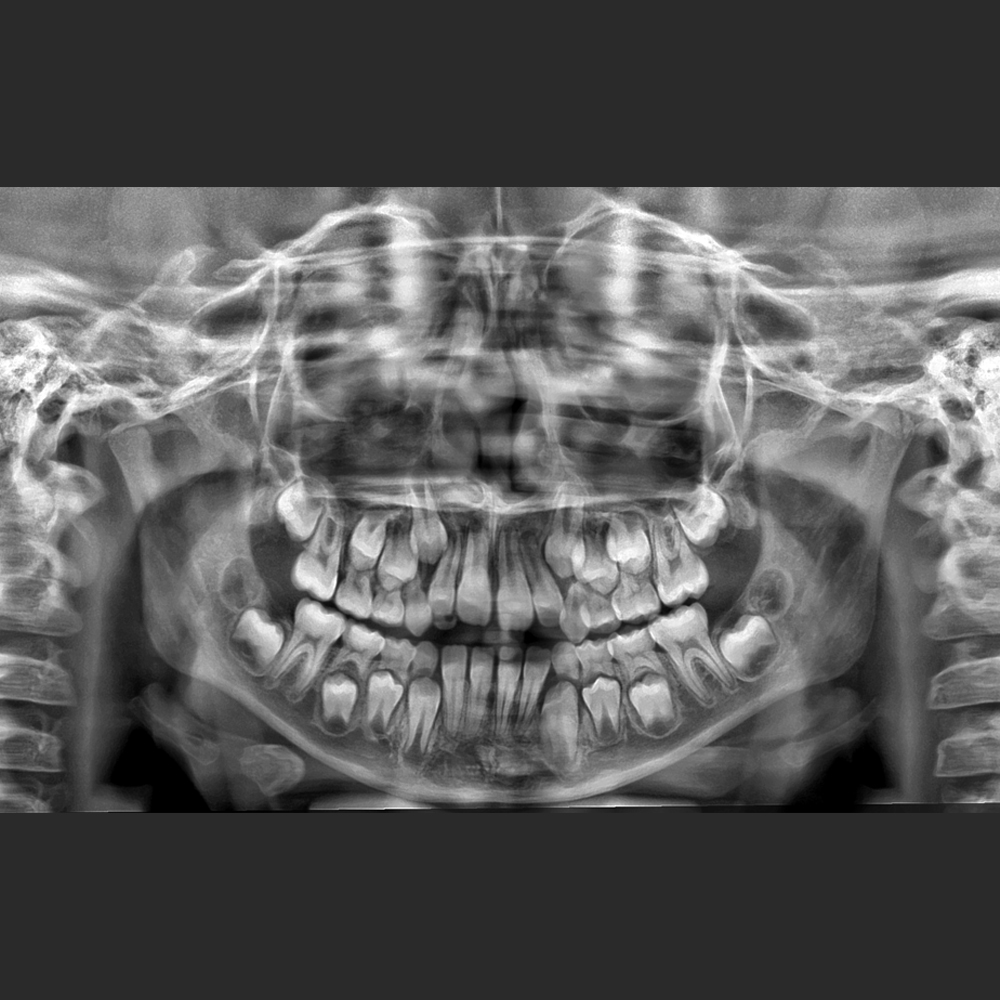

El Eagle 2D Pan/Ceph ofrece todos los exámenes en el perfil panorámico

(panorámica estándar, senos maxilares, baja dosis, bitewing, ATM, ortogonalidad perfeccionada, panorámica infantil y bitewing ortogonalidad perfeccionada)

A parte del perfil selecioado las imagenes son automacticamente procesadas y exhibidas dentro de los parametros del sharpen, brilho y contraste previamente determinado dando agilidad al flujo de trabajo.